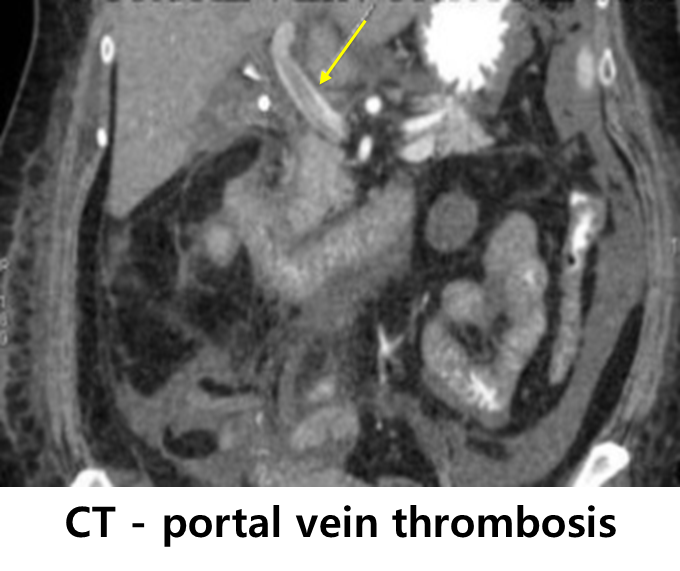

3) 간문맥 혈전증(portal vein thrombosis)

(1) 문맥고혈압에 의해 주로 발생하지만, 문맥고혈압을 추가적으로 악화시킬 수도 있음

(2) 진단: US/CT/MRI

(3) 치료: 항응고제 투여 고려(enoxaparin 등)

* 단, 많은 간경변 환자들이 응고장애 및 정맥류 발달 등으로 인해 적극적인 항응고 치료가 어려운 경우가 많다.